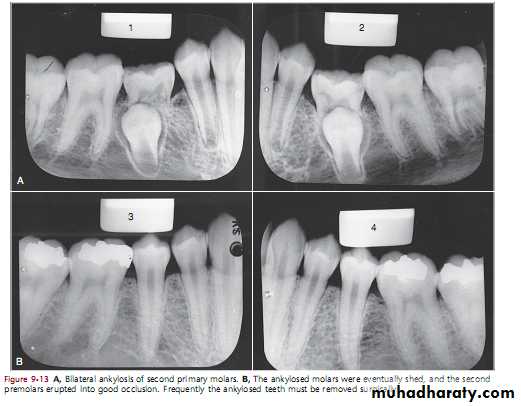

the ankylosed tooth is in a state of static retention, whereas in the adjacent areas eruption and alveolar growth continue and the tooth will be infra-occlussionThe mandibular primary molars are the teeth most often observed to be ankylosed

theoriesAnkylosed second primary molar with a carious lesion in the occlusal surface.

This tooth probably becameankylosed soon after root resorption began.

An ankylosed, deeply embedded second primary molar. Surgical removal of this tooth is indicated

early ankylosis of a mandibular second primary molar that was not diagnosed until the patient was 10 years of age; at that time the succedaneous second premolar was lying malposed “

Surgical removal of this tooth is indicated

The second primary molar is ankylosed and below the normal plane of occlusion.

There is evidence of root resorption and deposition of bone into the resorbedareas.

1. Opposing molars in the area seem to be out of occlusion

2. The ankylosed tooth is not mobile, even in cases of advanced root resorption3. Confirmed by tapping the suspected tooth and an adjacent normal tooth

The ankylosed tooth will have a solid sound, whereas the normal tooth will have a cushioned sound

The diagnosis of an ankylosed tooth

4. A break in the continuity of the periodontal membrane indicating an area of ankylosis is often evident

radiograph is often a valuable aid in making a diagnosis

1. When patient cooperation is good and recall periods are regular, a watchful waiting approach is best.

2. If loss of arch length is evident, the dentist may choose to keep the tooth under observation.

A tooth that is definitely ankylosed may at some future time undergo root resorption and be normally exfoliated.

3. The eventual treatment may involve surgical removal

TreatmentSometimes the ankylosed primary tooth shed by itself, if not extraction is the treatment